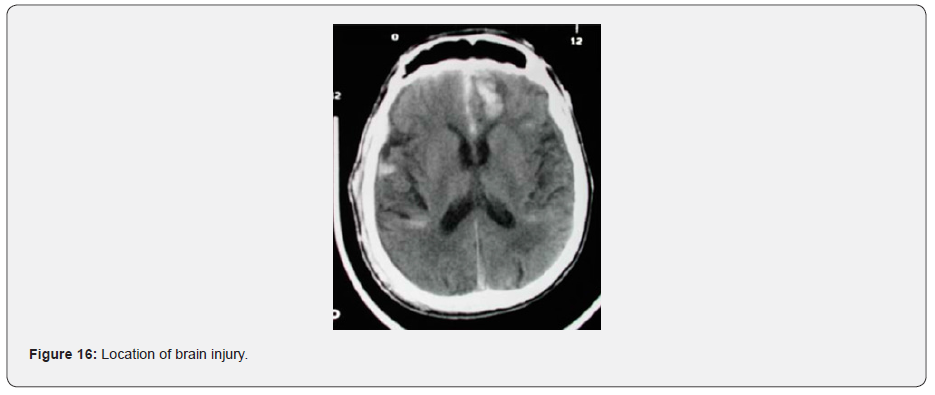

It can be observed that the strain level between the rods and the shells vary greatly, the rods being the lowest. This is expected as the rods have a restricted number of degrees of freedom, i.e. only able to stretch along their length. The shell model, on the other hand, is more flexible, hence it generates higher strains levels. What is consistent is the strain pattern between these two models, each predict higher strains in the frontal area on the bridging veins, as when the skull stops, the brain keeps moving, rotating about the contact area between the skull and the plate. This is illustrated clearly in (Figure 13), as well as being validated from the CT-Scan from the victim (Figure 16) [11].

The present study remedies these limitations and proposes a new bridging vein finite element shell model based on fabric material model with a linear response, as it has been evidenced in physical tests in the literature, that bridging veins were not sensitive to strain rate. The rupture level was calibrated against previous finite element work and material physical test data where the rupture was evidenced. From this work, it was concluded that a maximum principal strain of 15% was a plausible threshold level to capture bridging vein rupture. In the fall case studied, it was possible to extract and verify, with the help of a CT-Scan image, the location in the brain where bridging veins were torn.